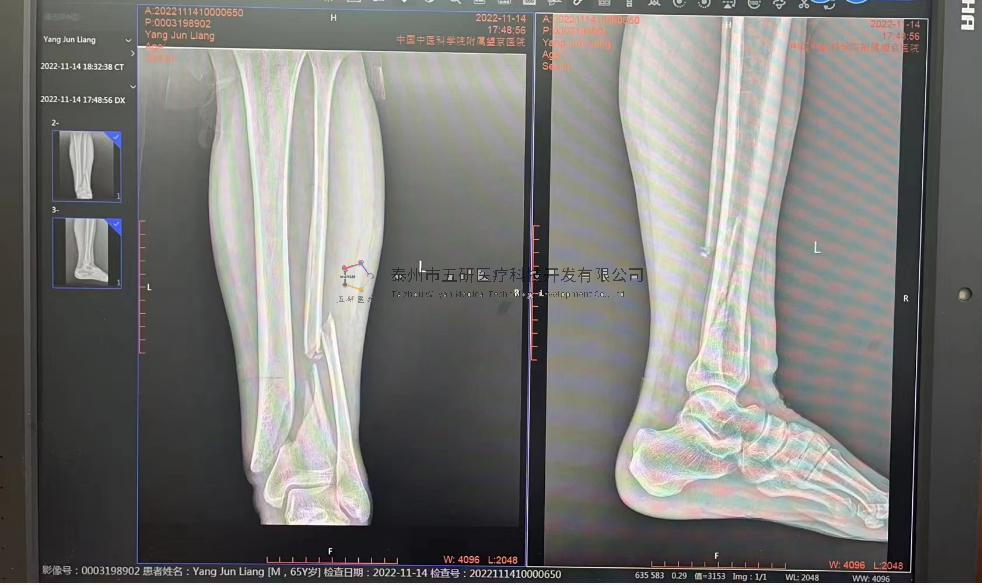

【基本資料】患者,男,65歲

【患者情況】脛骨遠(yuǎn)端骨折伴腓骨骨折

【影像圖片—術(shù)前】